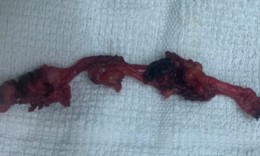

Việt kiều Mỹ 73 tuổi lựa chọn về Việt Nam phẫu thuật khối u đại tràng ác tính

Camera bệnh viện - 10/10/2025 14:55SKĐS - Việt kiều Mỹ 73 tuổi quyết định đến Bệnh viện Đa khoa Thủ Đức để thăm khám sau khi xuất hiện các dấu hiệu bất thường về đường tiêu hóa. Kết quả phát hiện khối u đại tràng ác nên nhanh chóng được phẫu thuật cắt bỏ.